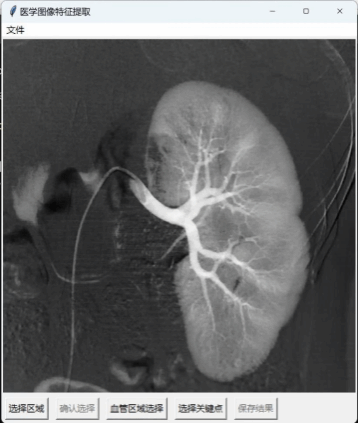

林炯宇正在开发一种基于深度学习的影像分析算法,该算法可以自动识别并量化肿瘤的多种特征,从而为临床医生提供更为精准的决策支持。除了影像组学研究外,林炯宇还参与了科室医疗器械相关创新项目研究,帮助临床医生减少对于医疗器械的关注,从而可以使其专心于手术过程本身。